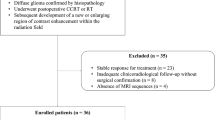

MR images of 70 patients treated with Gamma Knife SRS for WHO grade I meningiomas were retrospectively reviewed. MR acquisition included pre- and post-treatment DWI and DTI sequences, and subtractions were calculated to assess for radiation-induced changes in the parameter values.